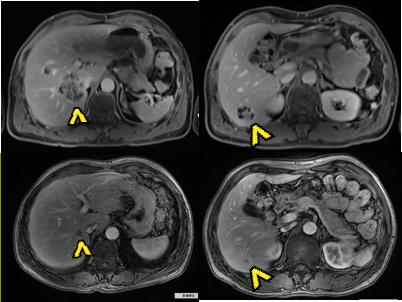

2019年10月至2020年2月:吉西他滨+顺铂 + PD-1*制剂抑** /Q21d,5周期,中间复查MRI示:病灶明显缩小。疗效评价PR。

2020年2月至2020年10月:PD-1*制剂抑**/Q21d,共12周。

疗效评价SD。

MRI示:免疫联合化疗后,病灶明显缩小。上图:治疗前;下图:治疗后